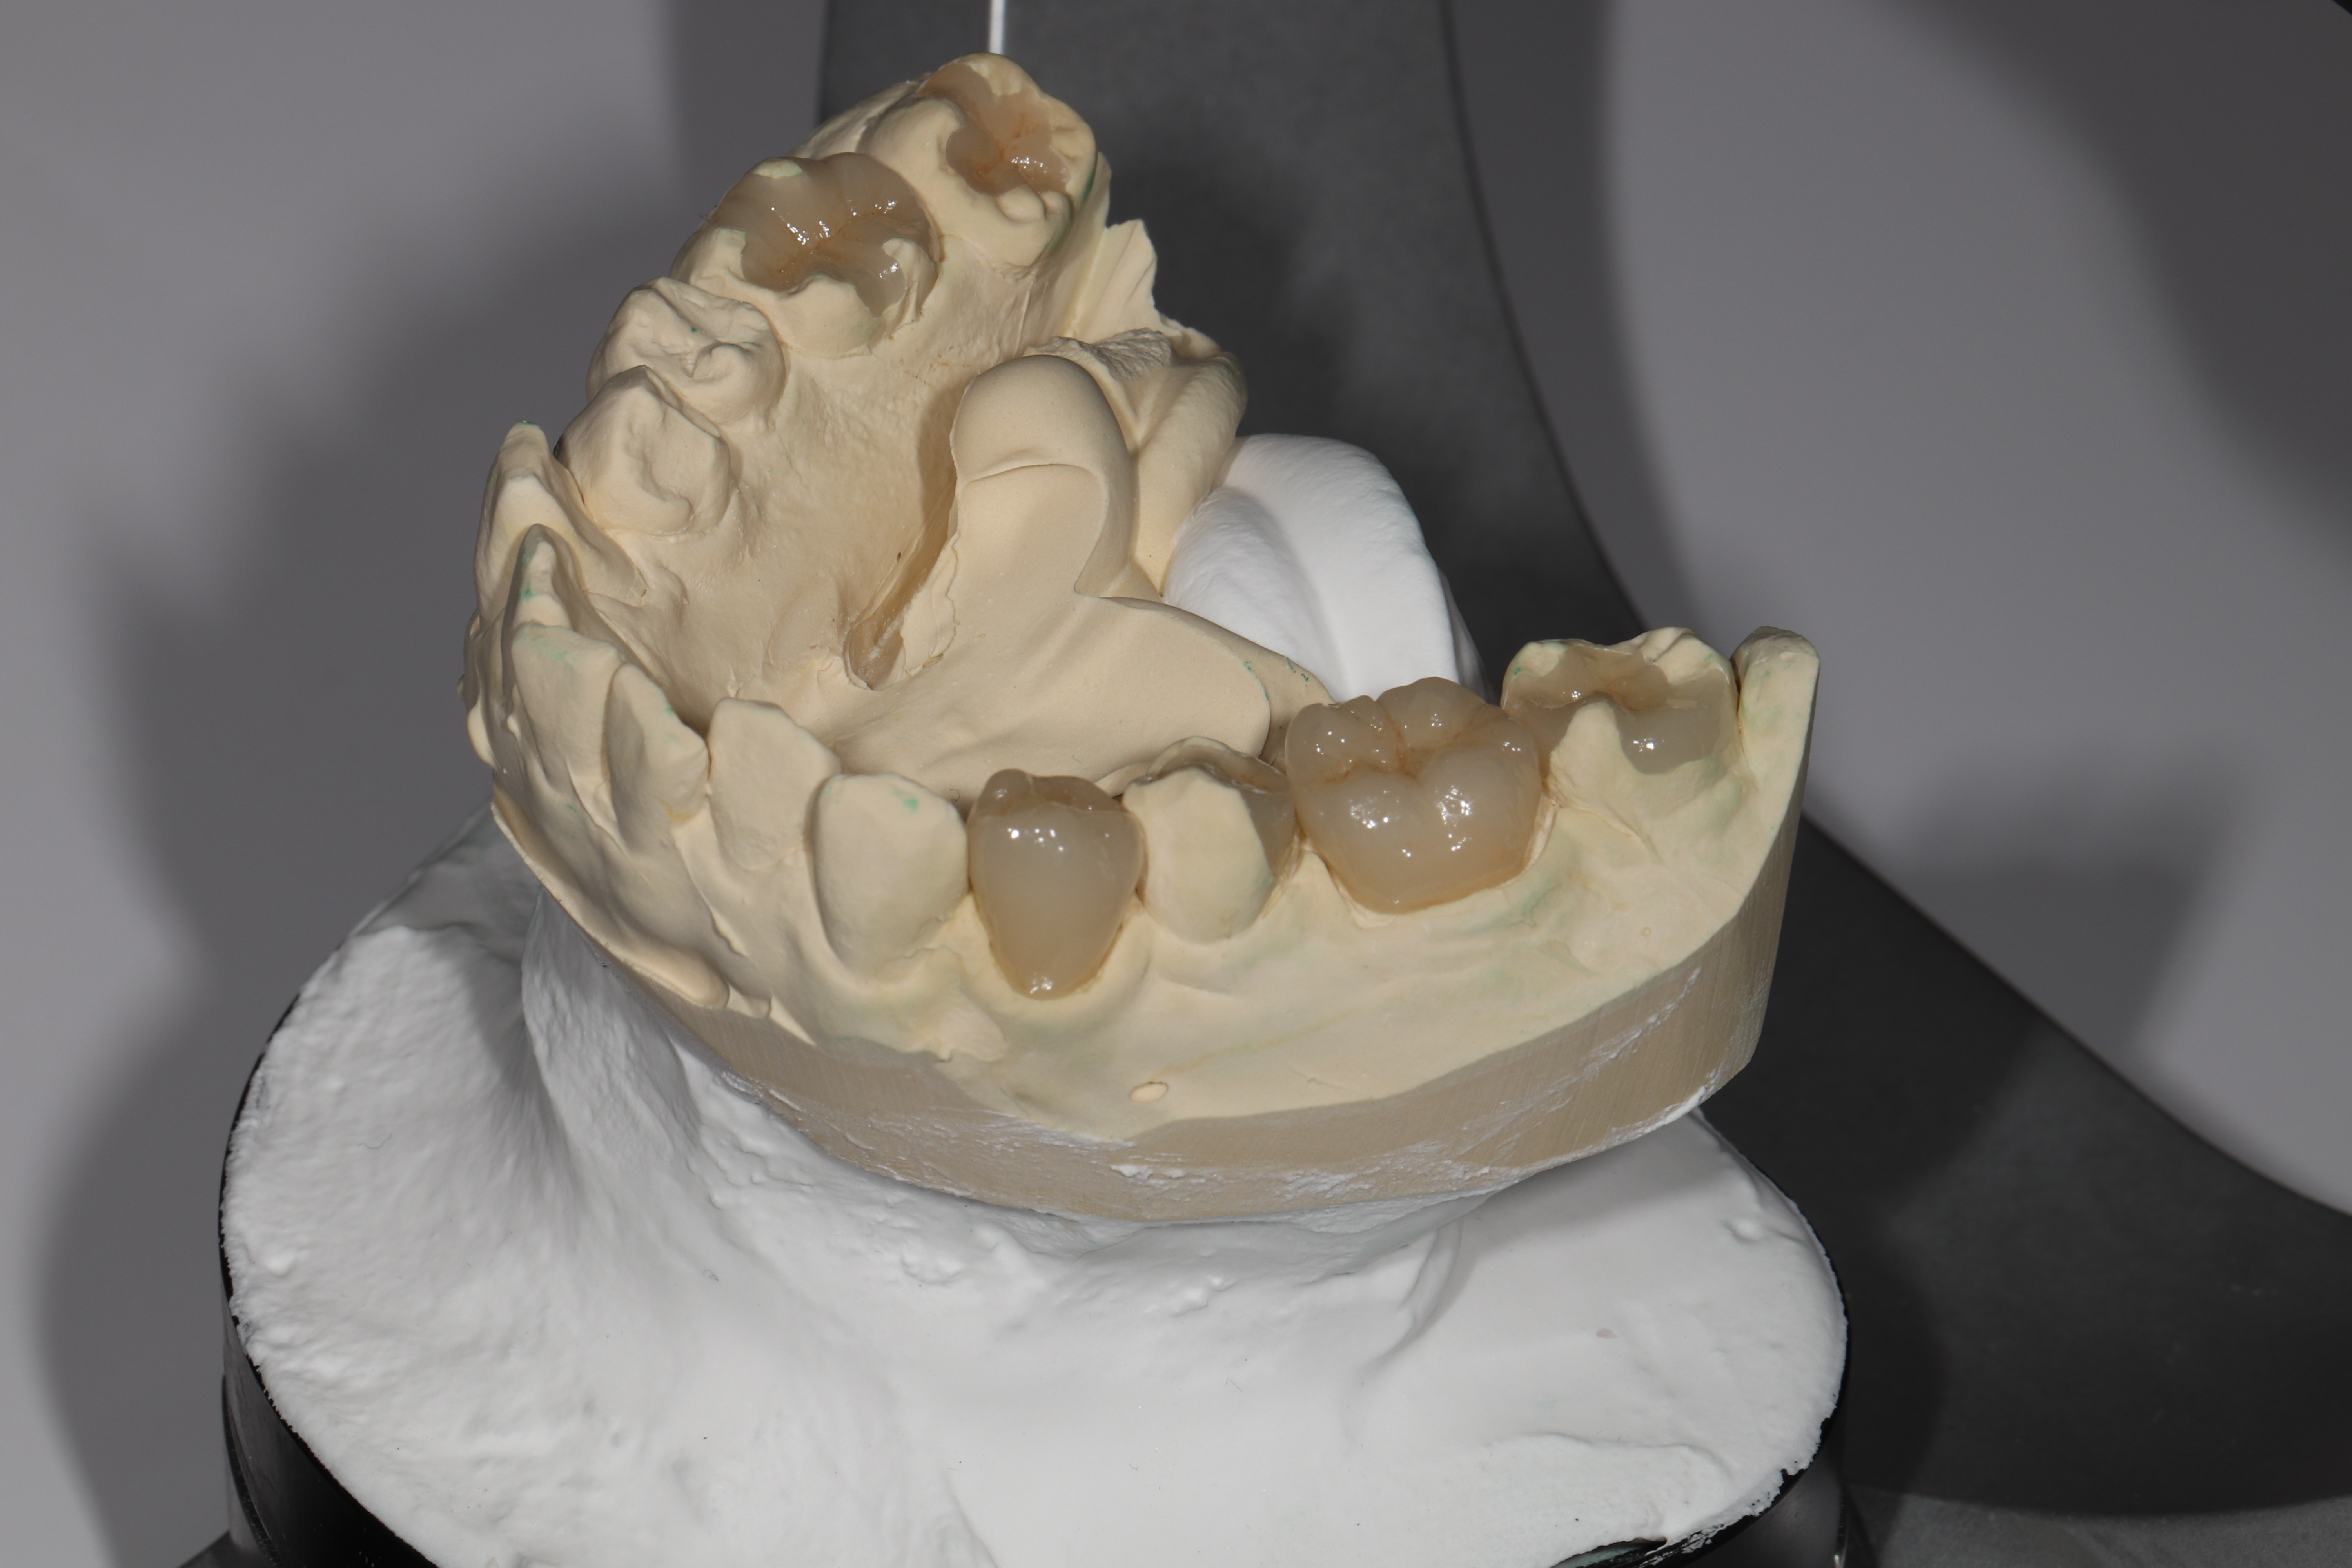

出来上がったセラミックです。

グラデーションがあるので、天然の歯と色を合わせる事が可能です。

色の変色はありません。

咬合器を用いて、噛み合わせと顎の運動を確認します。

フェイスボウを用いて診査を行う歯科医院は、日本では数が少ないです。